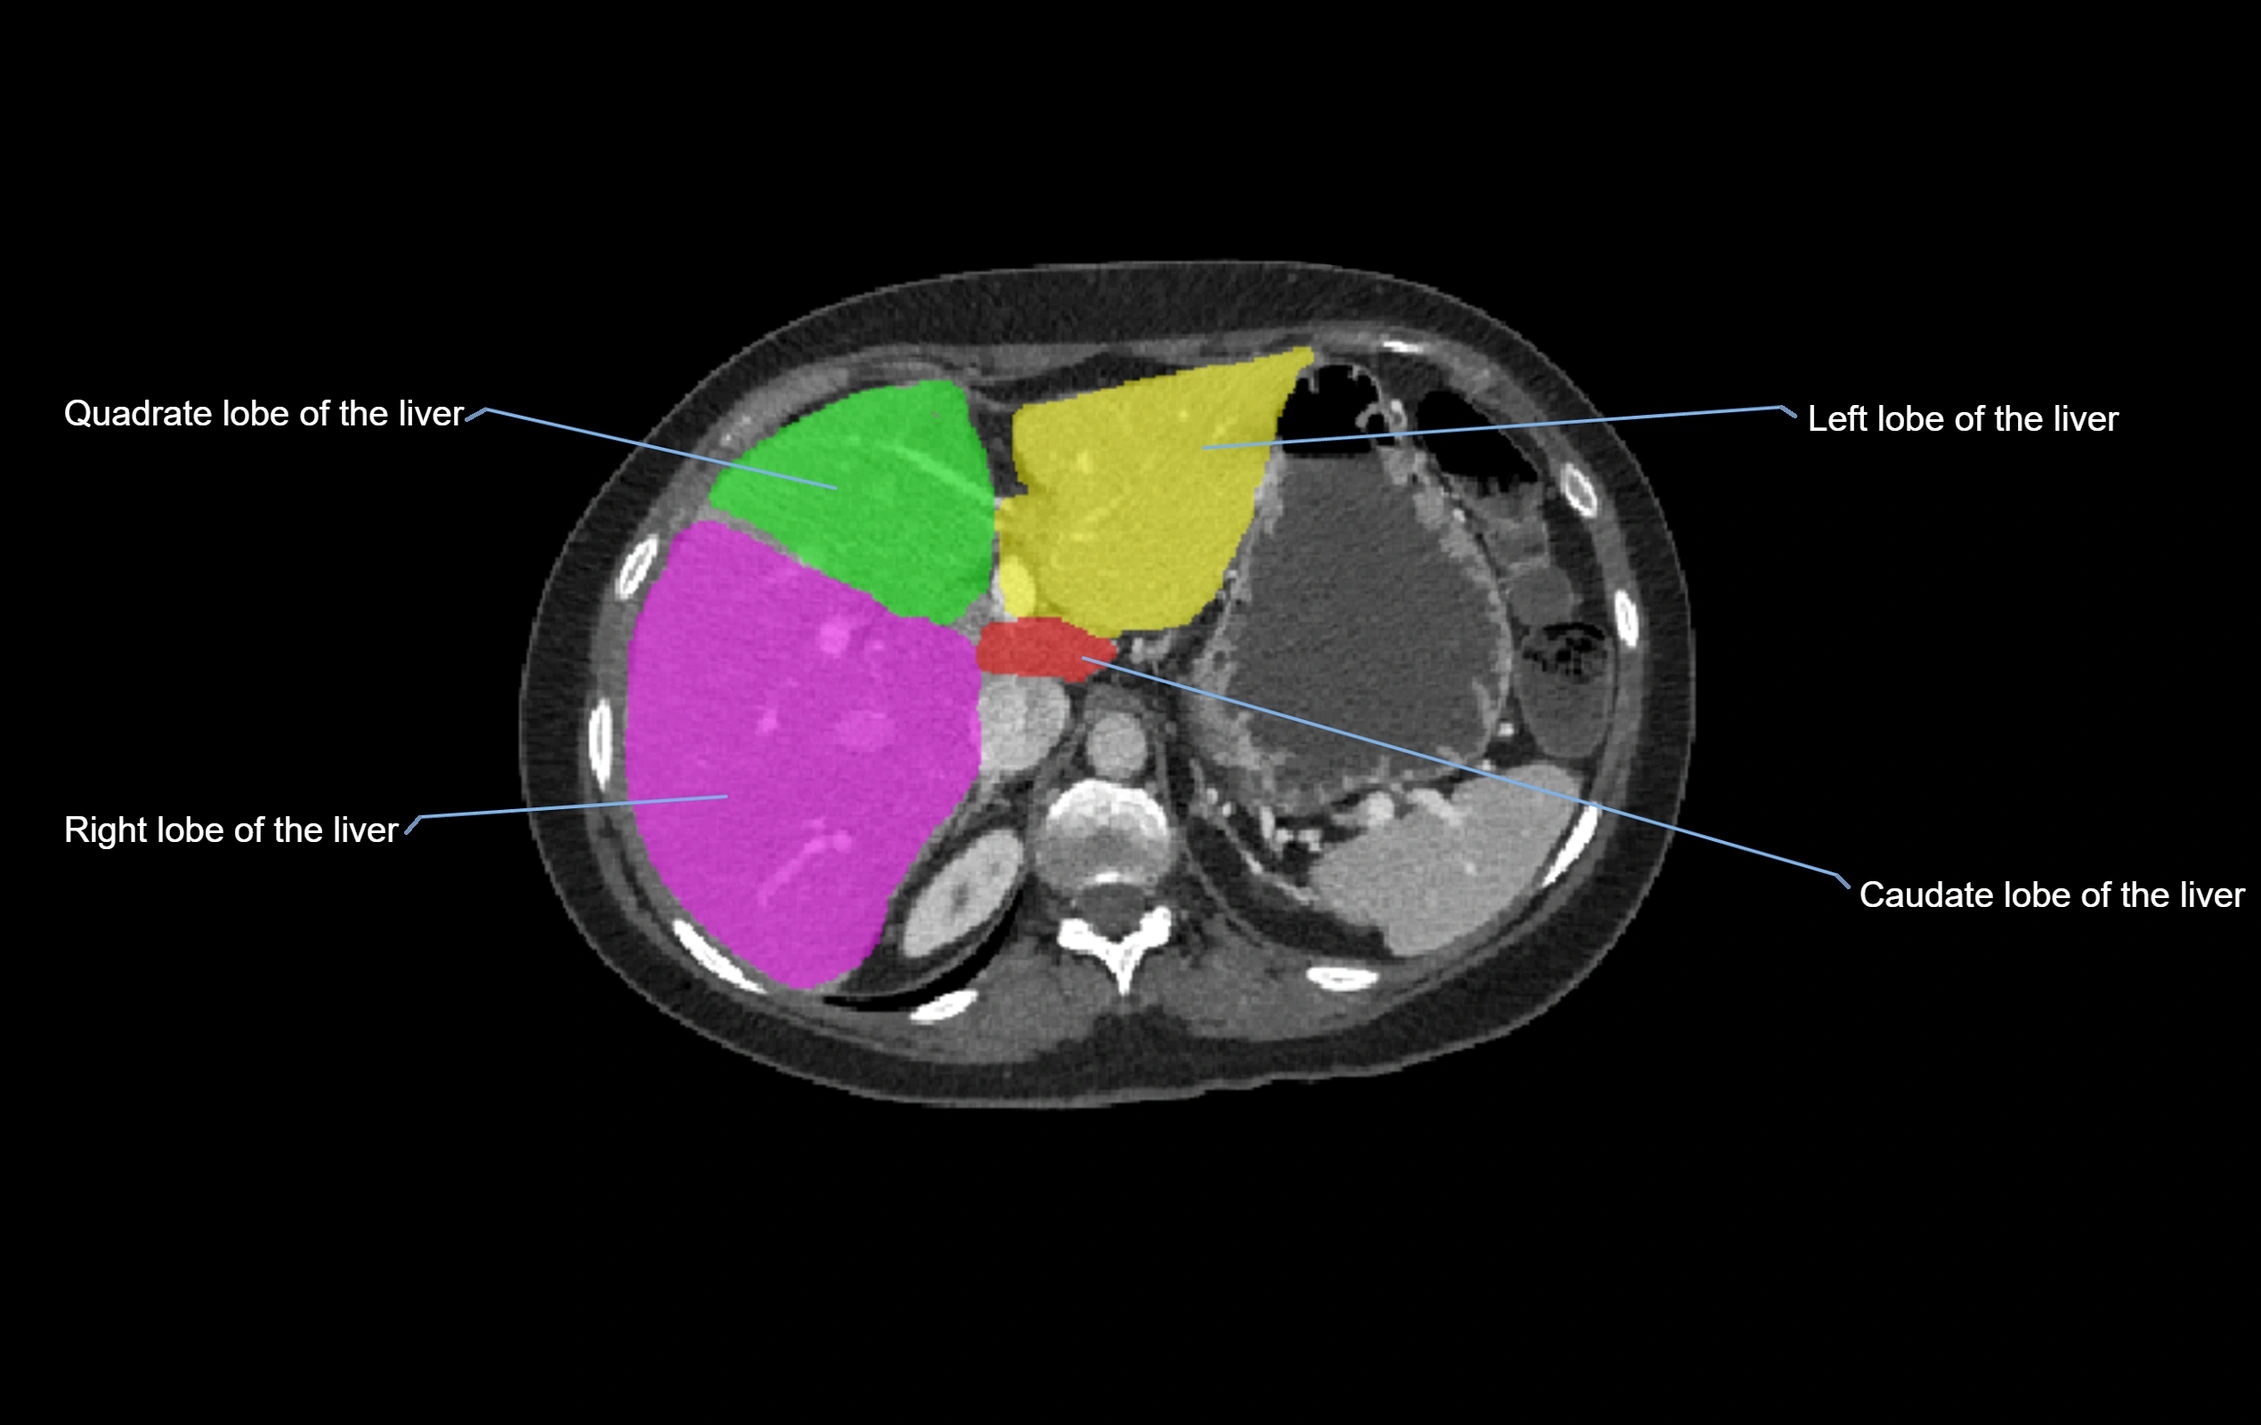

Caudate lobe of liver

The caudate lobe of the liver is a distinct anatomical subdivision of the liver, designated as segment I in Couinaud’s classification. It lies on the posterior surface of the liver, between the fissure for the ligamentum venosum (left boundary) and the groove for the inferior vena cava (IVC) (right boundary). Superiorly, it is related to the posterior liver surface, and inferiorly it is separated from the left lobe by the porta hepatis.

The caudate lobe is unique because it receives dual portal venous and arterial inflow from both the right and left portal veins and hepatic arteries. It also has independent venous drainage directly into the IVC via multiple small hepatic veins, unlike other lobes that drain through the three main hepatic veins.

This anatomical autonomy makes the caudate lobe especially significant in liver surgery, transplantation, and hepatic venous outflow obstruction syndromes (e.g., Budd–Chiari syndrome). Enlargement of the caudate lobe is a characteristic imaging feature in chronic liver disease and cirrhosis.

CT Appearance

CT Pre-Contrast:

• Caudate lobe appears as a soft-tissue density, isodense to the rest of the liver

• Enlargement may be appreciated in cirrhosis or Budd–Chiari syndrome

CT Post-Contrast:

• Homogeneous enhancement in the portal venous phase, similar to rest of liver

• Independent venous drainage into the IVC may be visualized

• Lesions follow characteristic CT enhancement patterns (HCC: arterial hyperenhancement with washout; hemangiomas: peripheral nodular enhancement with centripetal fill-in)

CT Venous Phase (functional significance):

• Caudate lobe often enhances relatively more than other lobes in Budd–Chiari syndrome, due to preserved venous outflow

CT Image

image